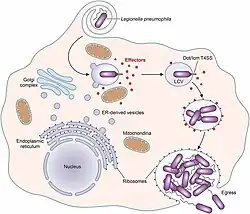

.jpg)

L. pneumophila is able to invade and replicate within human alveolar macrophages. Internalization of the bacteria appears to occur through phagocytosis or coiling phagocytosis and is reliant on Dot/Icm type 4B secretion system (T4BSS). Once internalized, the Dot/Icm system begins secreting bacterial effector proteins that recruit host factors to the Legionella containing vacuole (LCV). This process prevents the LCV from fusing with the lysosomes that would otherwise degrade the bacteria. Vesicles of the host cell's rough endoplasmic reticulum are attracted to the LCV, and these vacuoles supply the LCV with necessary lipids and proteins.[13] LCV membrane integrity requires a steady supply of host lipids, such as cellular cholesterol and the cis-monounsaturated fatty acid, palmitoleic acid.[31][32] L. pneumophila replication occurs within the LCV. Once nutrients are depleted, the bacteria gain flagella and cytoxicity. To exit the host cell, L. pneumophila lyses the LCV and resides in the cytoplasm. In the cytoplasm, L. pneumophila inhibit organelle and plasma membrane function and structure which ultimately leads to osmotic lysis of the host cell.[33]

Legionella-containing vacuole

For Legionella to survive within macrophages and protozoa, it must create a specialized compartment known as the Legionella-containing vacuole (LCV).[37] Through the action of the Dot/Icm secretion system, the bacteria are able to prevent degradation by the normal endosomal trafficking pathway and instead replicate. Shortly after internalization, the bacteria specifically recruit endoplasmic reticulum-derived vesicles and mitochondria to the LCV while preventing the recruitment of endosomal markers such as Rab5a and Rab7a. Formation and maintenance of the vacuoles are crucial for pathogenesis; bacteria lacking the Dot/Icm secretion system are not pathogenic and cannot replicate within cells, while deletion of the Dot/Icm effector SdhA results in destabilization of the vacuolar membrane and no bacterial replication.[38][39]